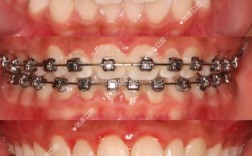

末端回弯与试戴

将弓丝插入磨牙颊面管,用持针器将末端向舌侧回弯1-2mm,防止弓丝脱出;将弓丝放入患者口腔,检查是否与所有托槽贴合,让患者做正中咬合、张口动作,确认无黏膜压迫、无咬合干扰,若有不适,取出后用梯形钳微调。